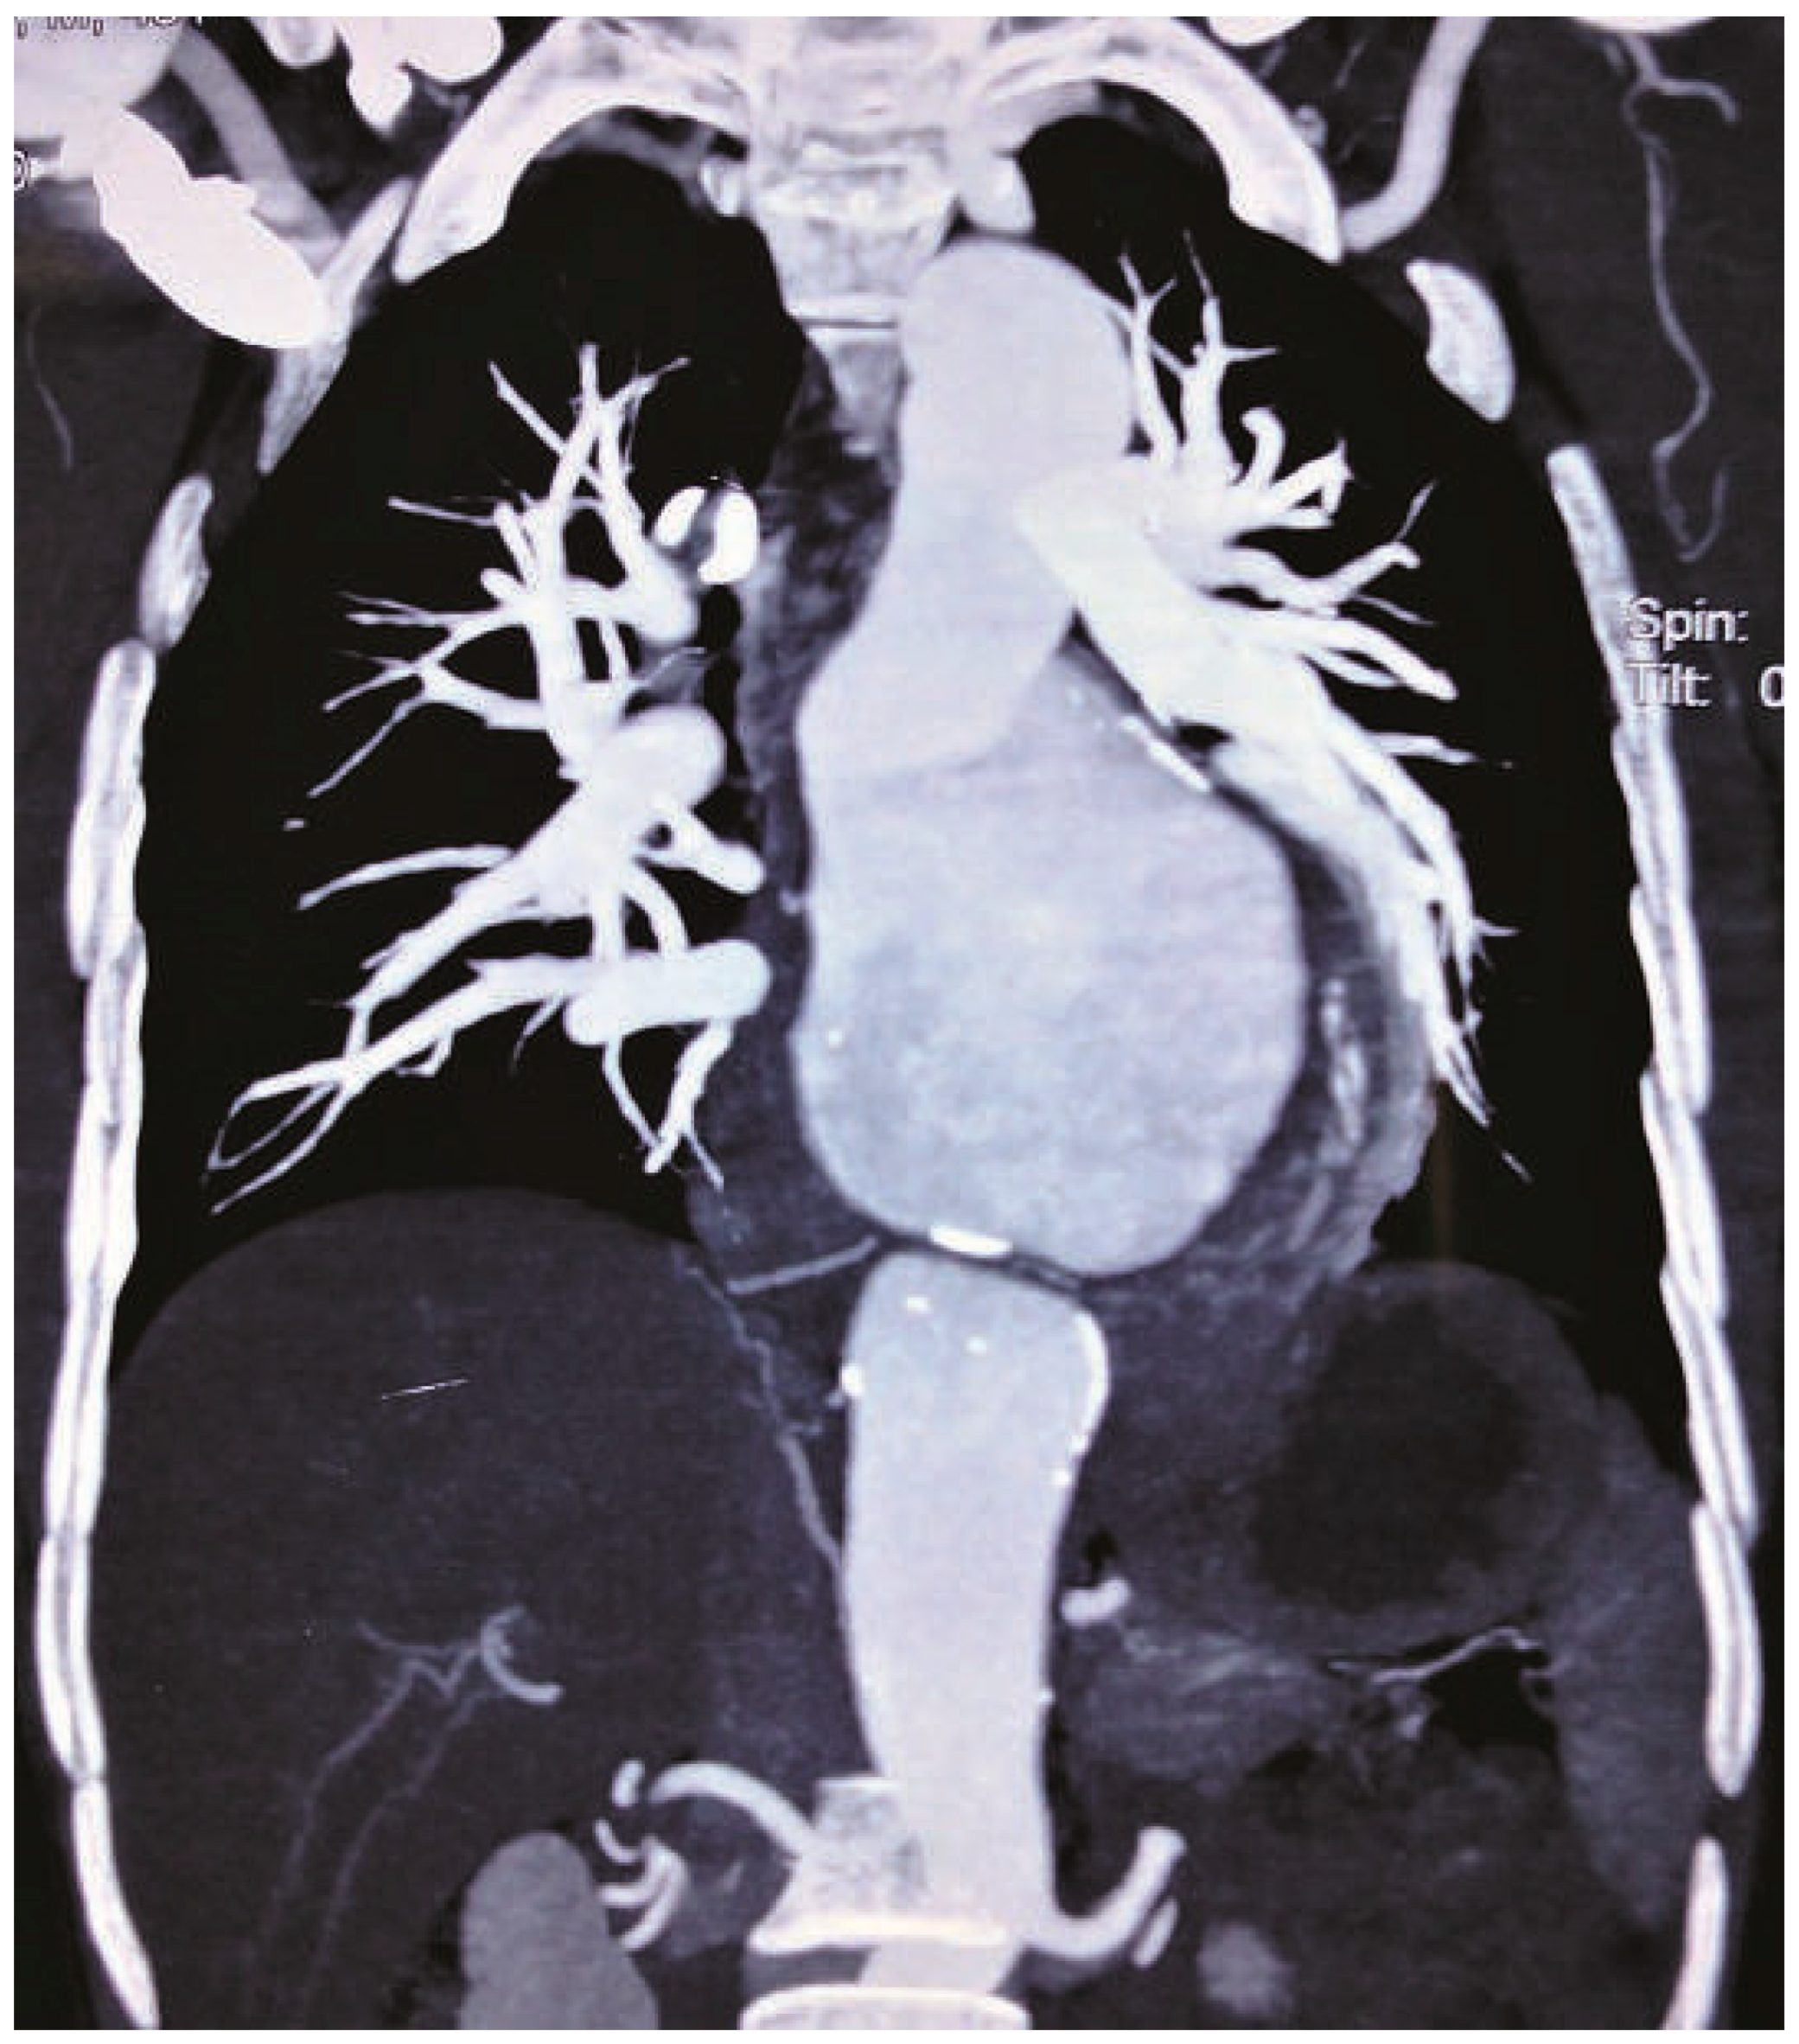

Neo Snowman in X-Ray

Case report